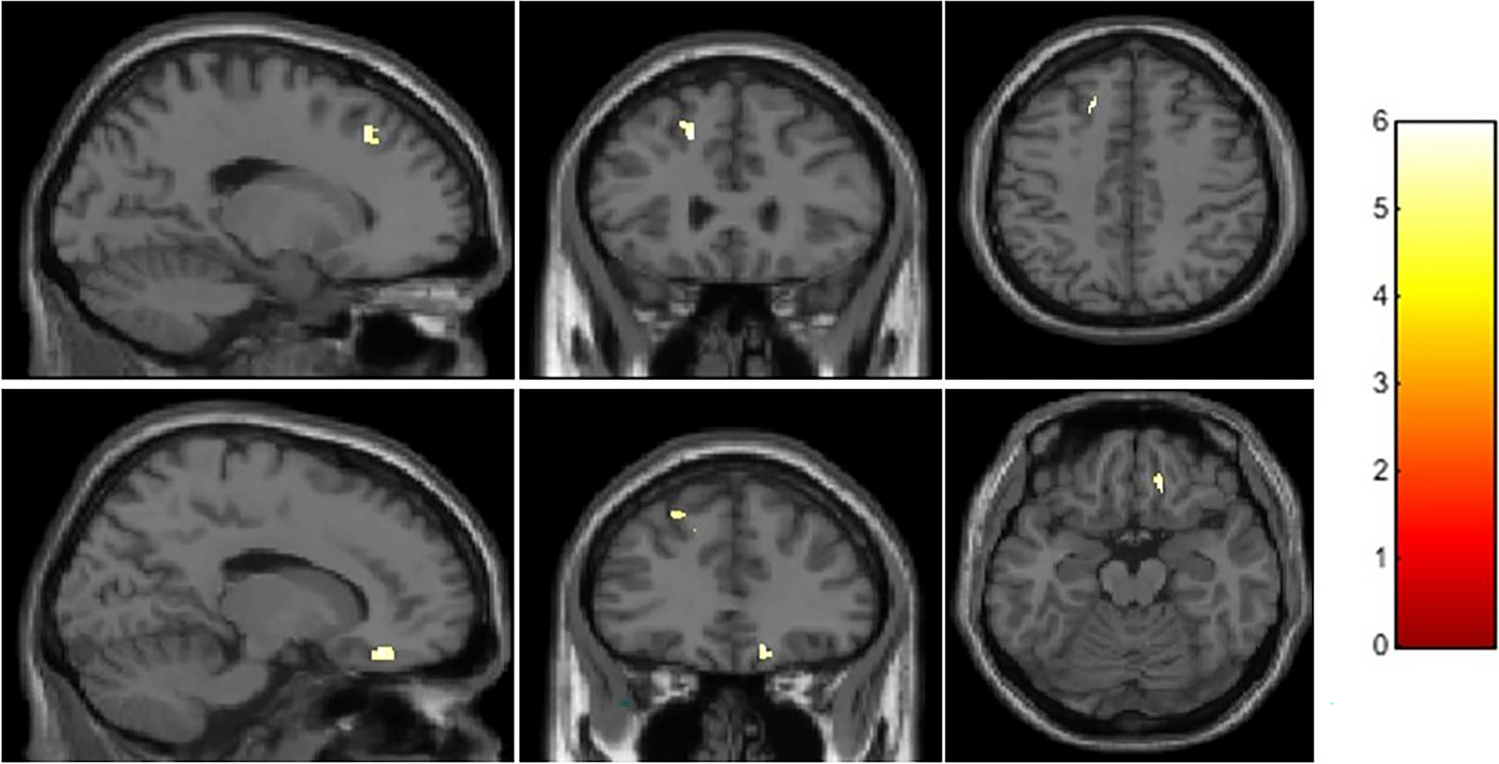

Figure 3

Statistical parametric maps overlaying averaged T1-weighted images show significantly smaller grey matter volume in the left superior and middle frontal gyrus (x = −15, y = 29, z = 42, cluster extent = 110) and right orbitofrontal cortex (x = 15, y = 35, z = −18, cluster extent = 54) in smokers compared with healthy non-smokers.